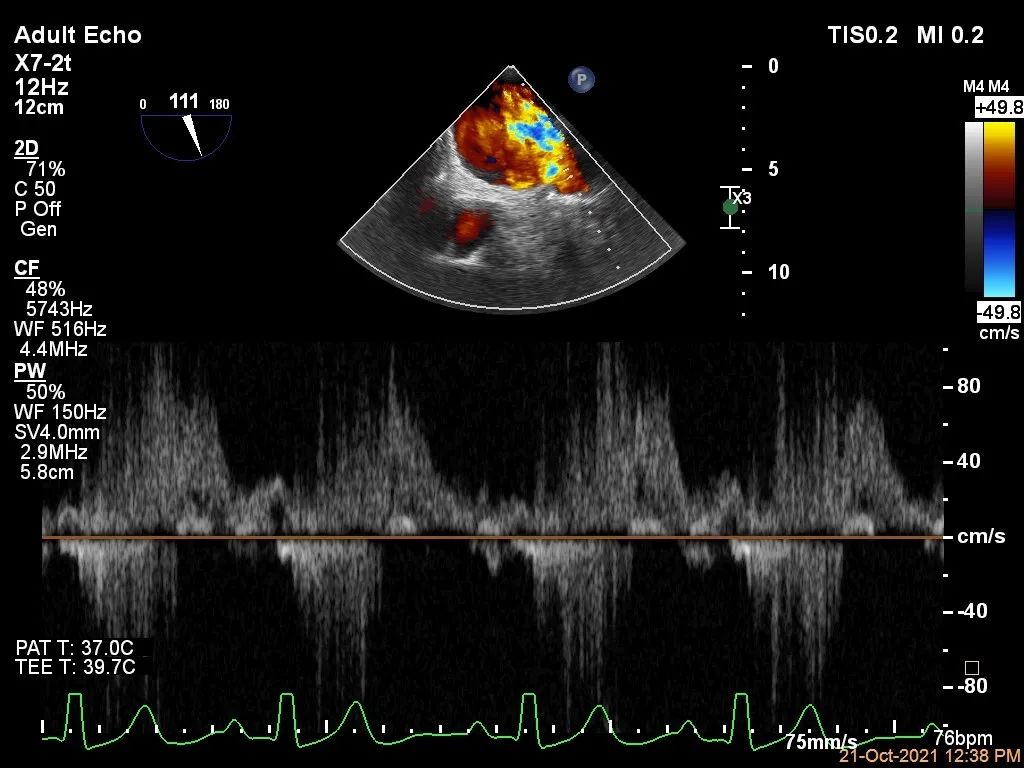

肺静脉血流频谱呈收缩期反向

肺静脉血流频谱恢复正向趋势

肺静脉血流频谱完全恢复正向